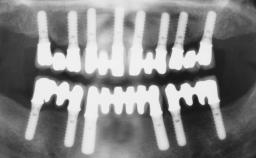

Immediate Loading of Four Implants in the Mandible and Six Implants in the Maxilla and Final Restoration with a Full-Arch Metal Framework FDP and a Full-Arch CAD/CAM Zirconia Framework FDP

A 65-year-old female patient with a failing residual maxillary dentition and a complete mandibular removable denture was referred for consultation and treatment. The patient’s chief complaint was that her upper residual teeth were mobile and she was unable to chew. The patient also asked us to improve the esthetic appearance of her smile. The patient’s desire was a stable and comfortable dentition in both jaws, and she specifically asked for a fixed rehabilitation. The patient reported a history of recurrent caries, endodontic complications, and periodontal disease as main reasons for previous teeth extractions. The anamnesis was negative for bruxism and TMJ disorders. The patient had no systemic diseases, was not on any medication,and did not smoke. The extraoral examination revealed a medium lip line, a wide diastema between the two central incisors (which, according to the patient, had appeared recently), and a partial collapse of the perioral soft tissues, probably due to loss of the correct vertical dimensions.

# of Implants 10